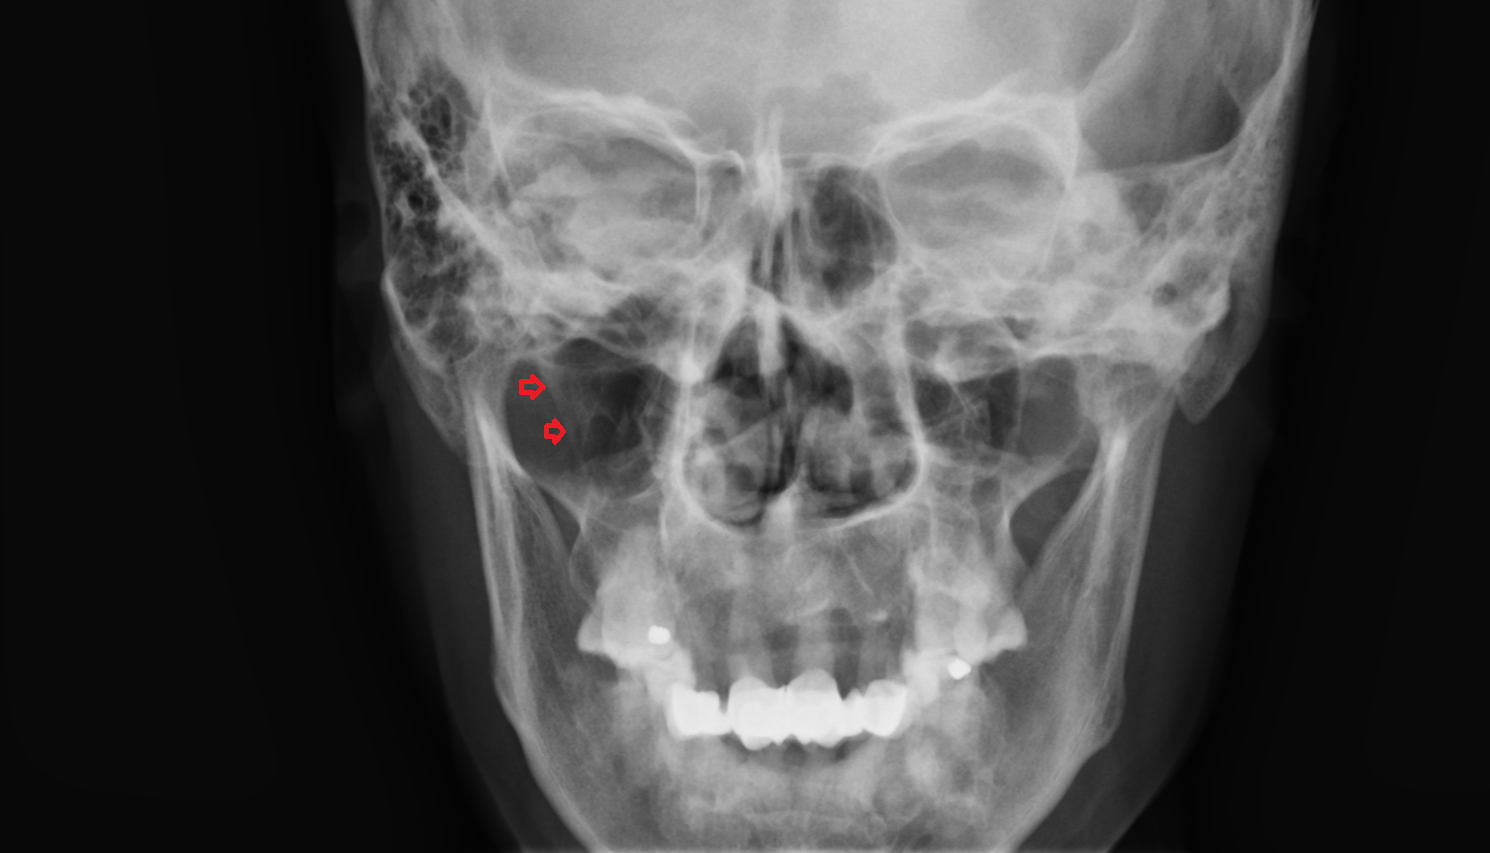

- Temporomandibular joint

- Mandibular condyle

- Mandibular fossa

- Zygomatic arch

- Zygomatic bone